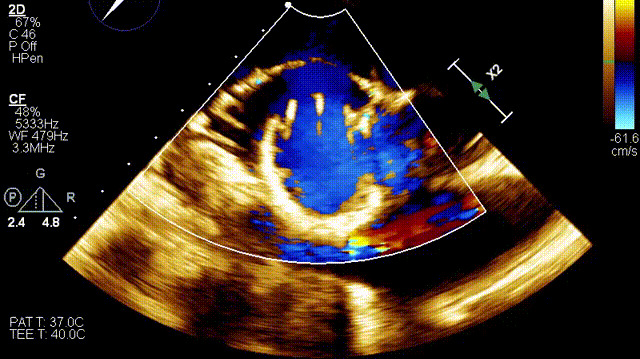

術(shù)后超聲

在這一研討會上,廈門大學(xué)心血管病醫(yī)院王焱教授帶領(lǐng)的結(jié)構(gòu)性心臟病團隊,分享了應(yīng)用LuX-Valve Plus經(jīng)血管三尖瓣置換系統(tǒng),為一例超高齡三尖瓣重度反流患者開展經(jīng)血管三尖瓣置換手術(shù)。整個手術(shù)過程順利,術(shù)后患者三尖瓣反流顯著改善,標(biāo)志著LuX-Valve Plus經(jīng)血管三尖瓣置換系統(tǒng)在福建省的再一次成功實踐,為三尖瓣介入治療的醫(yī)學(xué)循證添磚加瓦。